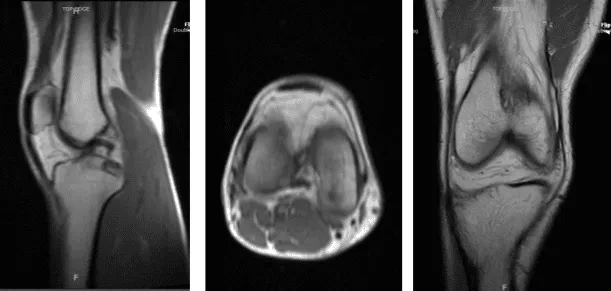

The patient is a 40-year-old male who came into the office after being involved in a car accident. He attempted conservative care, such as physical therapy and anti-inflammatory drugs, but these were ineffective. An MRI revealed an osteochondral defect of the lateral femoral condyle.

MRI Right knee non-contrast